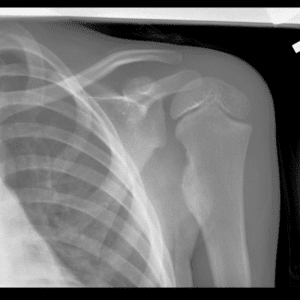

Pediatric Radiographs